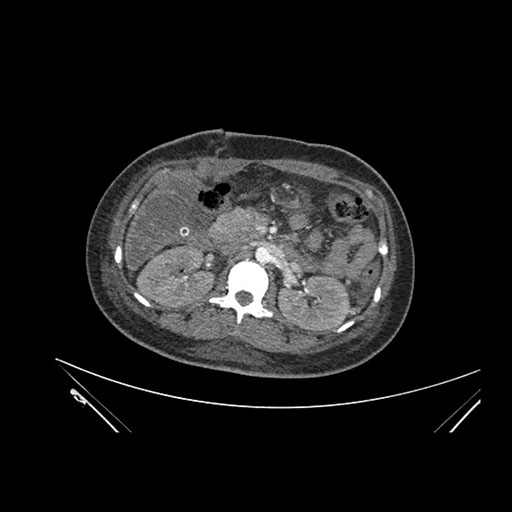

Imaging Analysis

Look through the patient's CT scan to identify any areas of concern for the necessary procedure.

Axial Venous

Based on initial findings, which issue(s) would you be most concerned about?